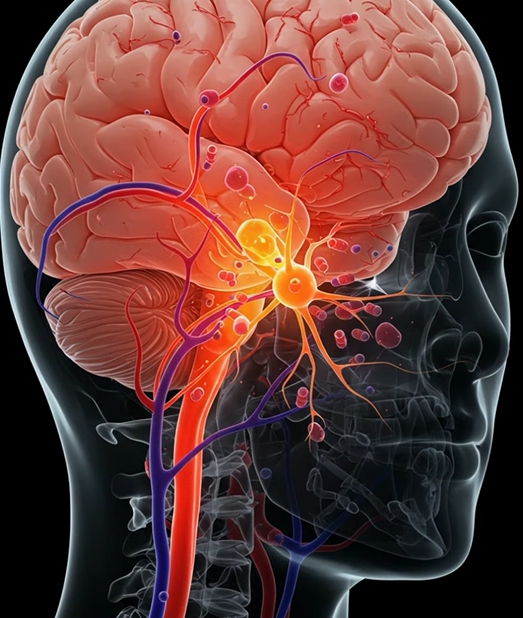

패혈증이란 세균, 바이러스, 곰팡이 등의 감염에 대해 우리 몸의 면역 반응이 과도하게 일어나면서 장기 기능 이상까지 초래하는 전신 염증 반응을 의미합니다. 쉽게 말해 감염 자체보다 몸의 과잉 반응이 장기를 손상시키는 상태입니다. 일반적인 감기나 폐렴 같은 감염 질환과 달리 빠르게 악화될 수 있어 조기 발견이 매우 중요합니다.

패혈증은 초기에는 단순 감기나 몸살과 비슷하게 시작되기 때문에 놓치기 쉽습니다. 하지만 면역 반응이 과도하게 활성화되면서 전신 염증 반응이 빠르게 진행되는 것이 특징입니다.

특히 호흡이 빨라지거나 정신 상태가 변하는 경우는 뇌와 폐에 산소 공급이 부족하다는 신호로 즉시 진료가 필요합니다. 고령자에서는 열이 없거나 오히려 체온이 떨어지는 경우도 많아 더욱 주의해야 합니다.

- 의식 저하, 혼수상태 → 뇌 기능 장애